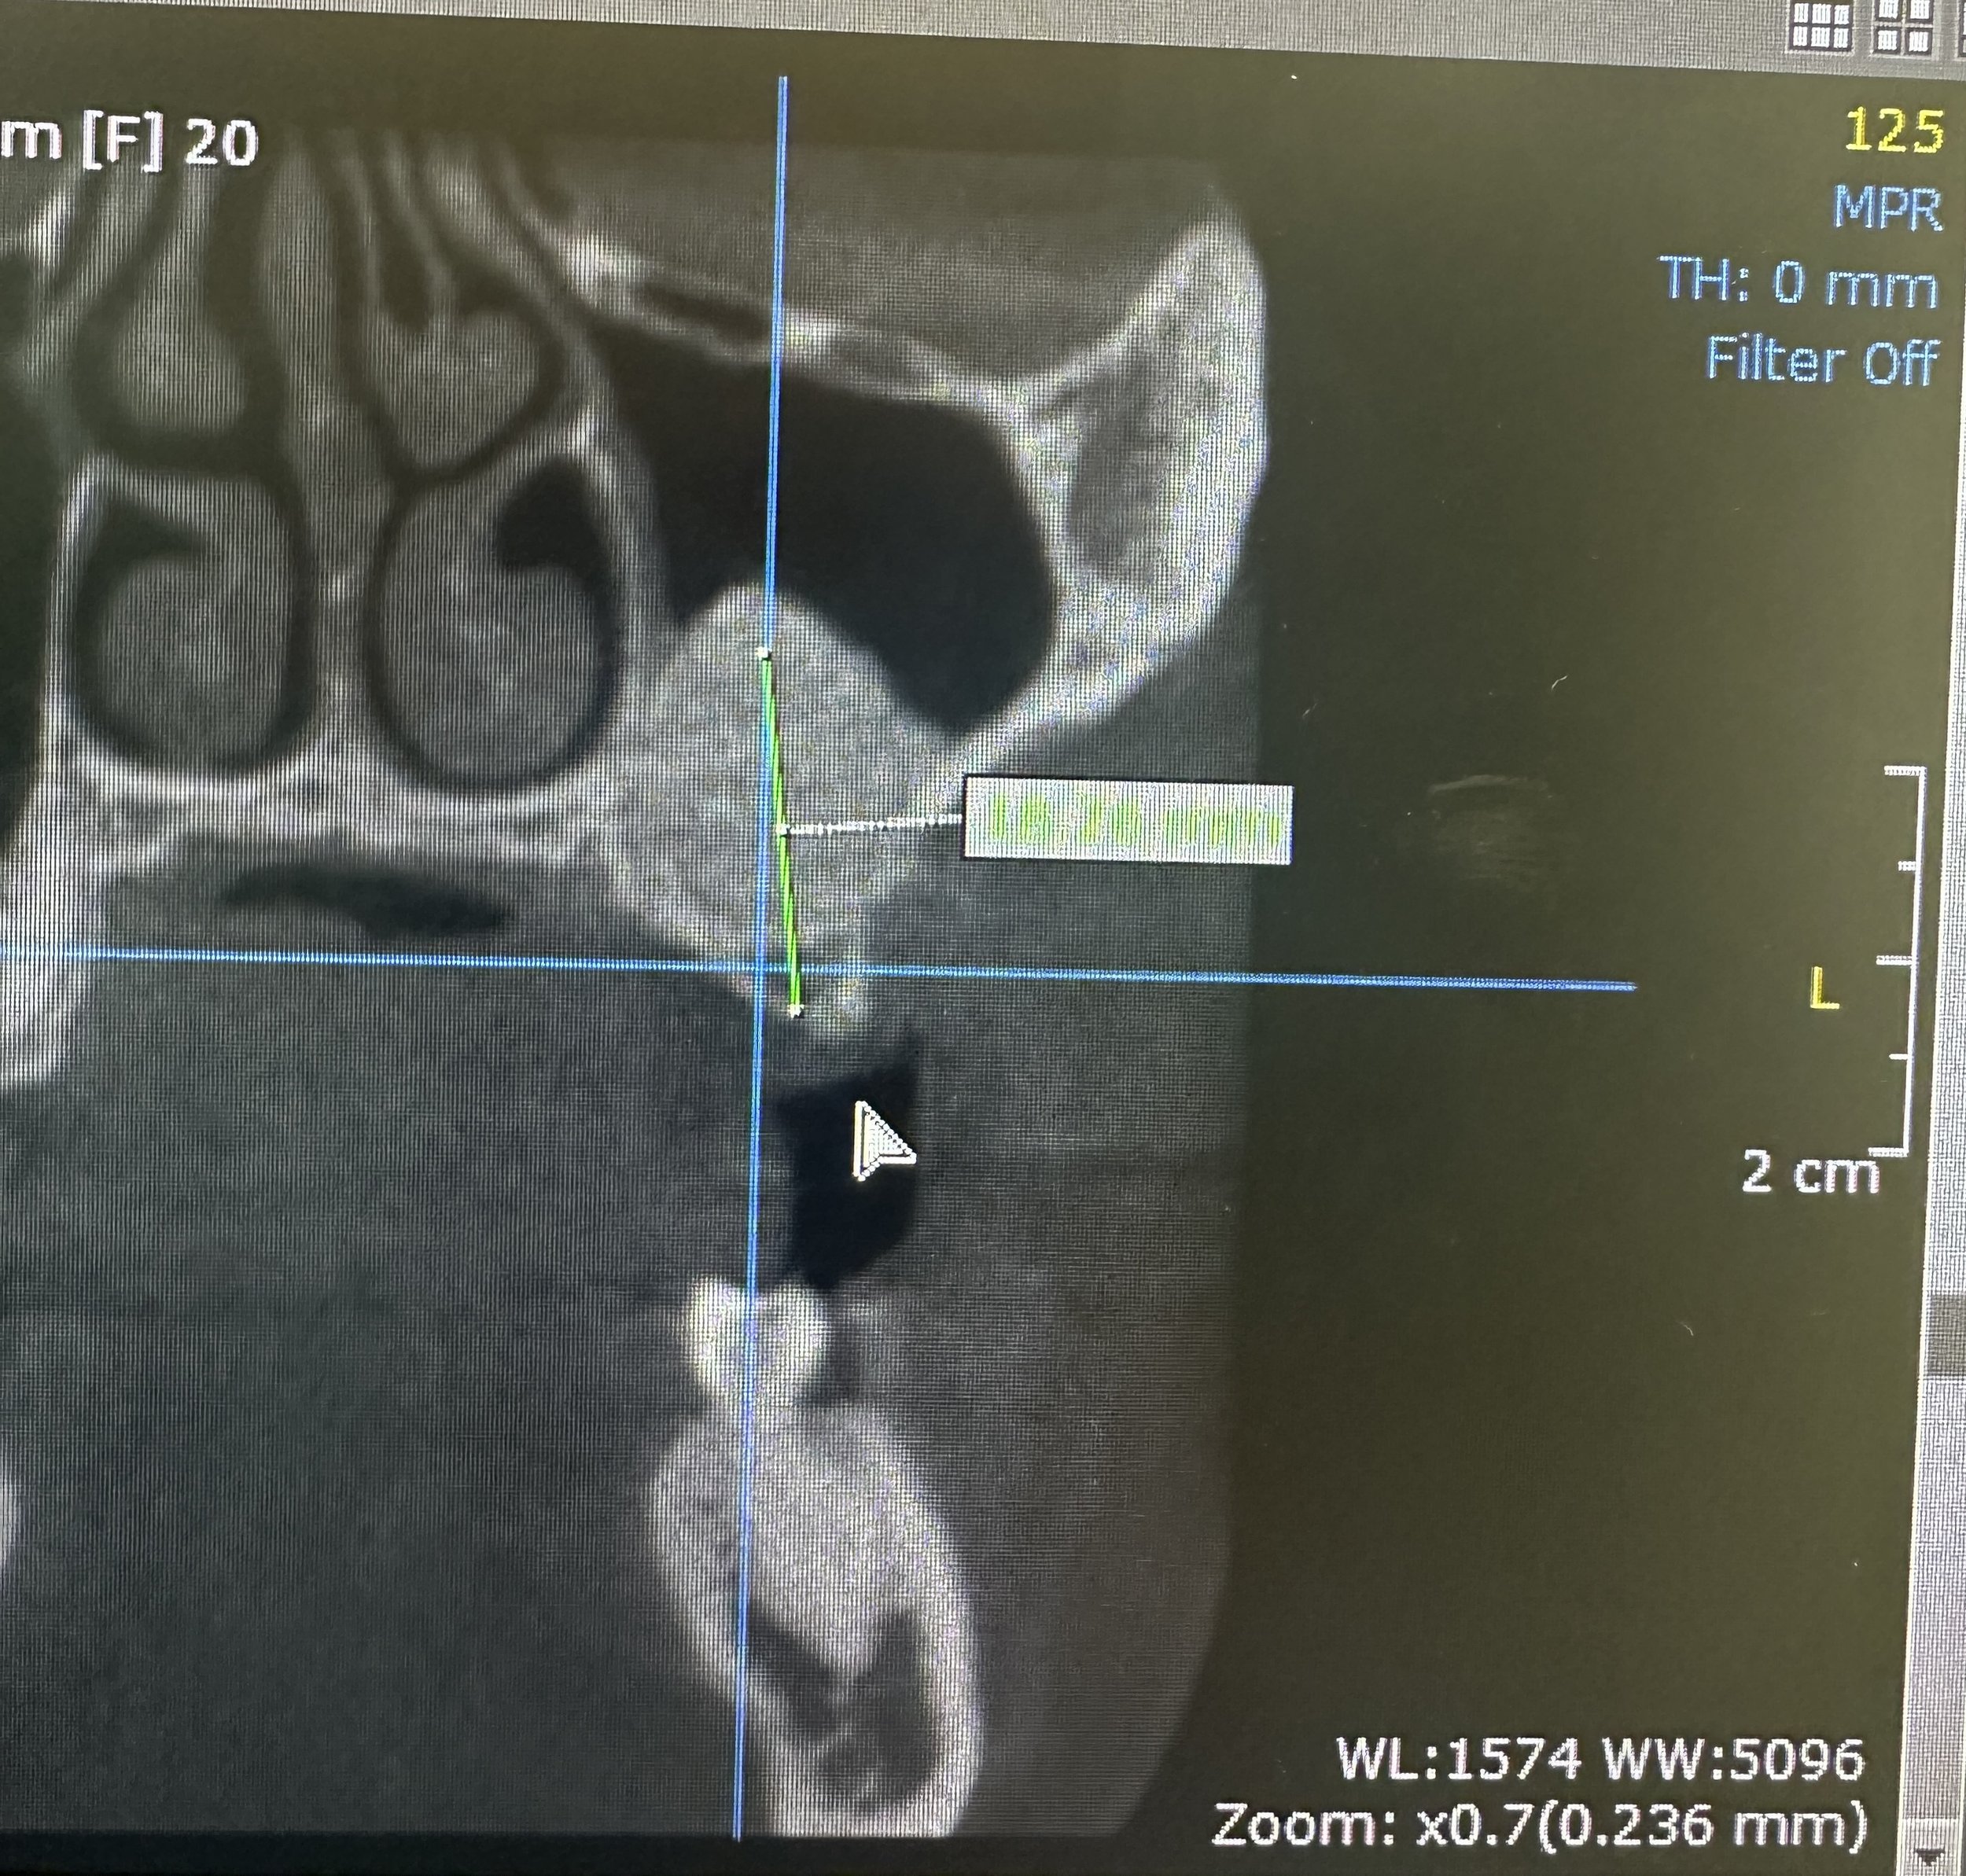

To restore the foundation for implant placement, a left maxillary lateral window sinus lift was performed. This technique allowed for controlled elevation of the sinus membrane and precise placement of bone graft material, increasing available bone volume while preserving surrounding anatomy.

Following adequate healing and bone maturation, implant placement at site #14 was completed with improved structural support and optimal positioning. Post-operative imaging demonstrated successful bone regeneration and stable integration of the implant within the augmented site.